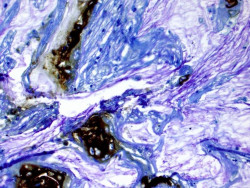

Identifican una nueva diana terapéutica que podría reducir la resistencia a la quimioterapia en cáncer de hígado

Dos estudios desarrollados por investigadores del CIBER de Enfermedades Hepáticas y Digestivas (CIBEREHD) y de la Universidad de León apuntan a una nueva diana terapéutica a la que dirigir fármacos para reducir la resistencia al sorafenib, el tratamiento estándar de primera línea utilizado en el cáncer de hígado avanzado, y mejorar la respuesta a la misma. Precisamente, el fracaso en esta quimioterapia es una de las causas del mal pronóstico del carcinoma hepatocelular (HCC), un tipo de neoplasia que supone la tercera causa de muerte relacionada con el cáncer a nivel mundial.